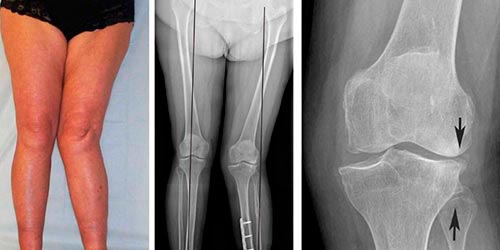

При артрозе коленного сустава 2 степени возникает грубый хруст при движении. Наблюдается общая невозможность передвигаться. При проведении рентгена видны большие области костных разрастаний, начинается субхондральный склероз, щель сустава сужается в два-три раза, по сравнению с показателями нормы.

Гонартроз коленного сустава 3 степени характеризуется утратой полноценного движения. Остаются только покачивания пораженным суставом. Он очень сильно деформируется. После рентгена можно увидеть отсутствие суставной щели. Сама поверхность расширена из-за разрастания ее краев. Деформирование остро выраженное, имеется уплотнение обоих эпифизов.

Рентгенография проводится в двух проекциях, чтобы получить изображение со всех сторон. Для достоверного отображения патологических процессов часто проводится многосторонний рентген здорового колена. После этого производится сравнение.